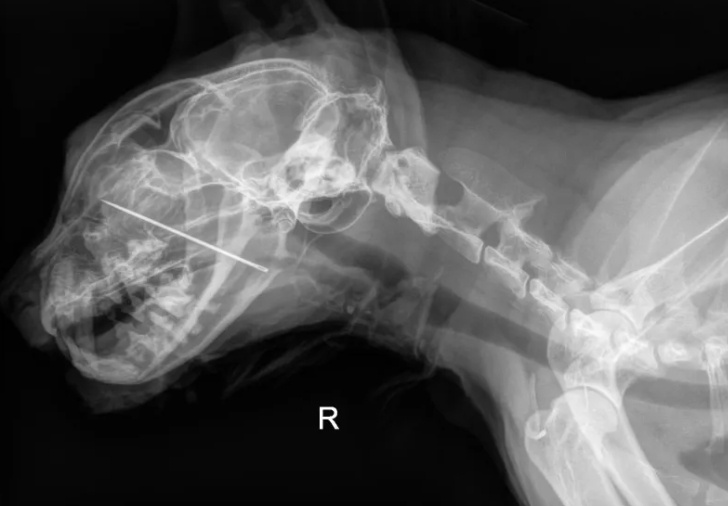

隨後,醫院轉介凱文到DoveLewis動物醫院,醫生們決定進行更為深入的檢查。經過X光片的詳細觀察,醫生們終於揭開了問題的真相:一根縫紉針竟然卡在了凱文的鼻腔中,這是導致牠嘔吐和吞嚥困難的根本原因。